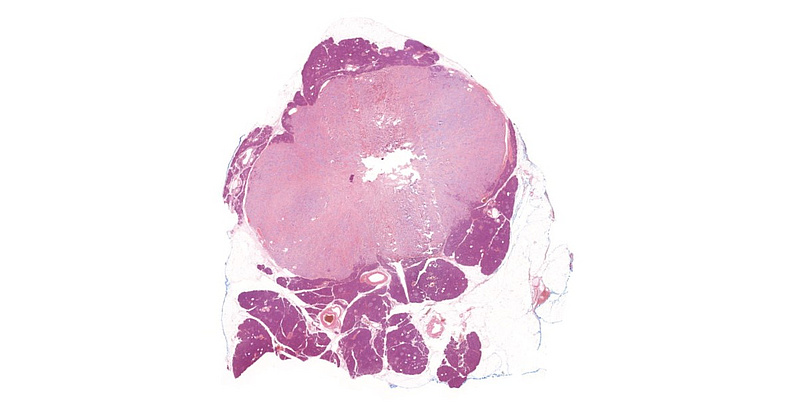

Macroscopic examination revealed a well circumscribed, slightly lobulated, whitish-yellowish tumor, corresponding to the tumor identified by CT and MRI.

On low power, we noted a nest-forming, occasionally rosettoid tumor with expansive border (Panel A). The tumor cells were monomorphic with ample, eosinophilic cytoplasm, salt-and-pepper chromatin and occasional inconspicuous nucleoli. Mitoses were not observed. No necrosis. The stroma of the tumor consisted of exuberant, dense, hyalinic collagen with central calcification (Panel B). No lymphovascular or perineural invasion was identified. Immunohistochemistry revealed a diffuse cytoplasmic positivity for synaptophysin (Panel C), perinuclear dotlike positivity for chromogranin-A (Panel D) and diffuse cytoplasmic positivity for Insulin (Panel E). The Ki-67 labelling index was less than 1% (Panel F).